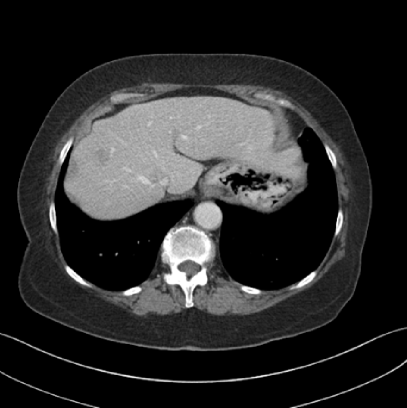

Refer to caption(a) Clinical Standard IRRefer to caption(a) Clinical Standard IR

Refer to caption(b) JENGRefer to caption(b) JENG

Refer to caption(c) Clinical Standard IRRefer to caption(c) Clinical Standard IR

Refer to caption(d) JENGRefer to caption(d) JENG

Figure 14: Qualitative clinical results from a thoracic CT staging dataset for a 12-year-old with osteosarcoma with pulmonary metastases. The clinical standard hybrid IR is shown on the left and JENG is on the right. (a) The clinical standard hybrid IR in lung window with a window center of -600 HU and a window width of 1500 HU. (b) JENG at a resolution comparable to the clinical standard, but with less noise and fewer artifacts. (c) The clinical standard hybrid IR in soft tissue window with a window center of 55 HU and a window width of 440 HU. A metastatic lung cancer nodule can be found in the left upper lobe. (d) JENG in soft tissue window at a comparable resolution, but with less noise and fewer artifacts. Note that JENG is not fully corrected for beam hardening artifacts.

Refer to caption

(a) Clinical Standard Hybrid IR

(b) JENG

Figure 15: An example cross-plane image from the same thoracic dataset as in Fig. 14. (a) A coronal-view image slice of the clinical standard hybrid IR in soft tissue window. (b) JENG at a comparable resolution but with reduced image noise and artifacts.

V.B. Clinical Cases